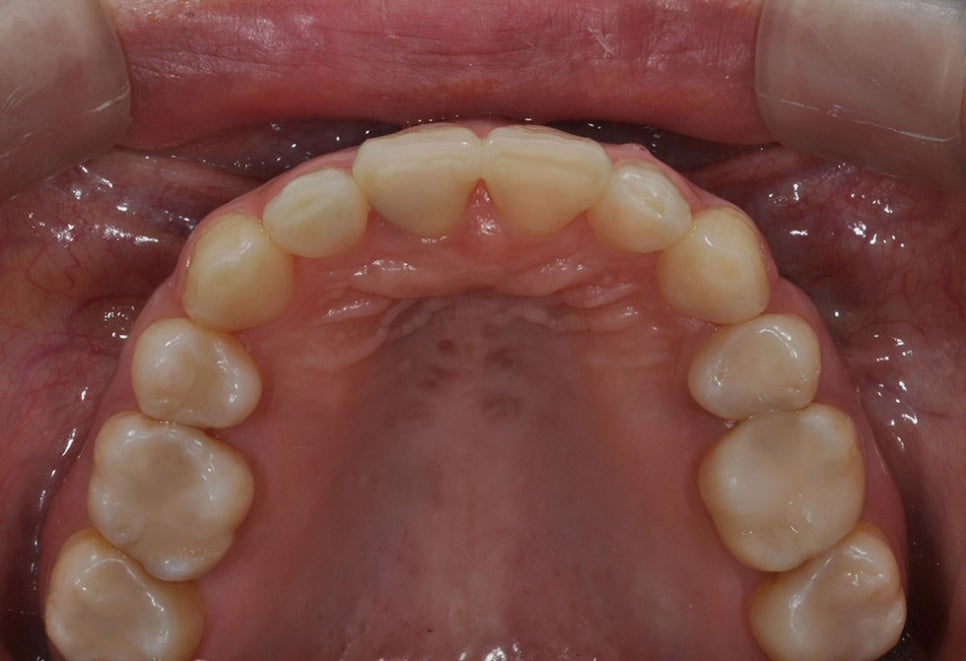

말합니다. 위 사진과 같이 거의 보이지 않는

교정 장치를 순서대로 끼는 것만으로

치아가 교정되는 것입니다.

부릅니다. 역삼동치아교정 투명하여

심미성이 뛰어나고 편리하며 치아 라인에

꼭 맞춰진 교정기로 교정 시 통증이

크게 경감될 뿐 아니라 치아 뿌리까지

명확하게 교정되는 장점이 있습니다.